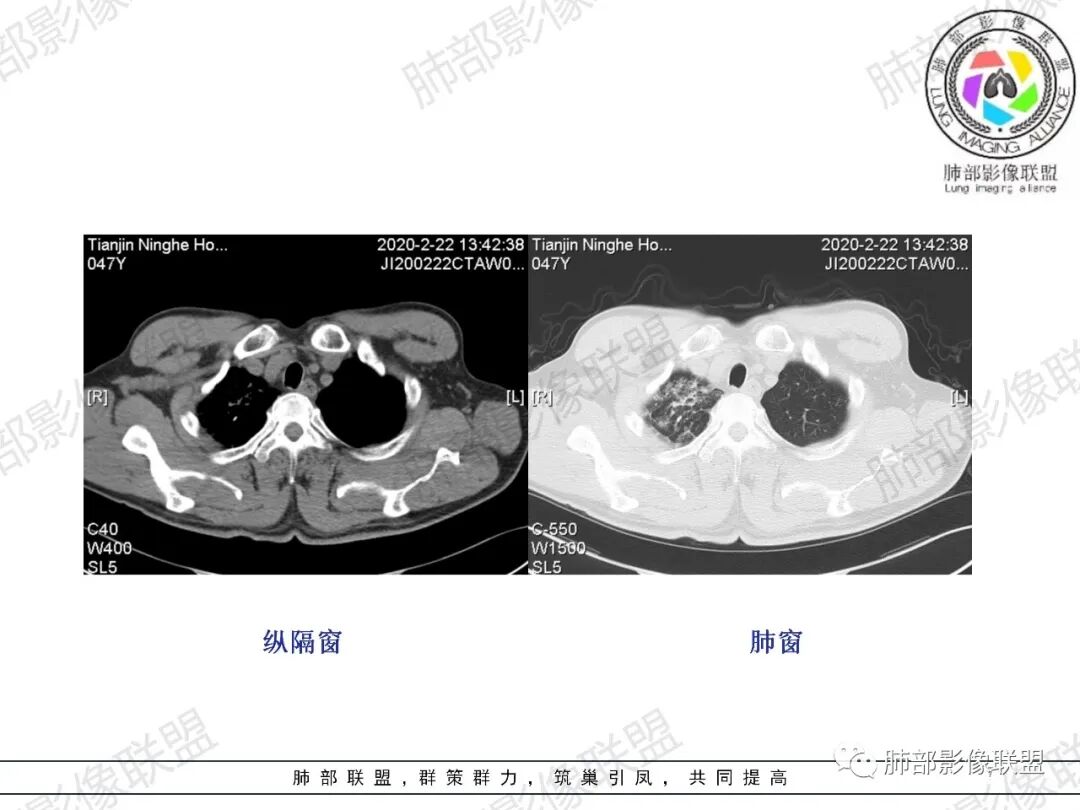

张延军:右肺上叶多发大小不等结节,部分界清,反晕征(+),下叶胸膜下磨玻璃影,纵膈窗似较对称血管细,结合咳血症状,考虑栓塞

小锁:中年男性患者,急性起病,胸闷气喘伴有胸痛,低热,低氧,白细胞增高。CT:右肺上叶斑片状稍高密度影,粟粒样树芽征,有钙化,考虑继发性结核;右肺下叶肺动脉增粗,溶冰征,提示血管来源病变,结合临床病史,考虑肺栓塞。

CT肺动脉成像(CTPA)以其高度的敏感度和特异度,已经作为临床上诊断急性肺栓塞的首选方法。

中央型肺栓塞包括栓塞部位累及纵隔动脉(肺动脉干,左、右肺动脉,左、右叶间动脉)及肺叶动脉(双肺上叶肺动脉、右肺中叶及左肺舌叶肺动脉、双肺下叶肺动脉);周围型肺栓塞包括栓塞部位累及肺段及亚段动脉(肺段动脉包括双肺上叶3支、右肺中叶及左肺舌段各2支、双肺下叶各5支)。

急性肺栓塞患者CTPA上胸部继发改变包括肺动脉干增粗、右心增大、肺梗死、马赛克征、Westermark征、心包积液、胸腔积液、肺不张/肺膨胀不良等。

肺动脉高压的标准以肺动脉干直径大于3 cm或肺动脉干直径大于同层面升主动脉直径。右心增大的标准以横断位四腔心层面右心室内径与左心室内径比值大于1,或出现室间隔变直或凹陷等征象。